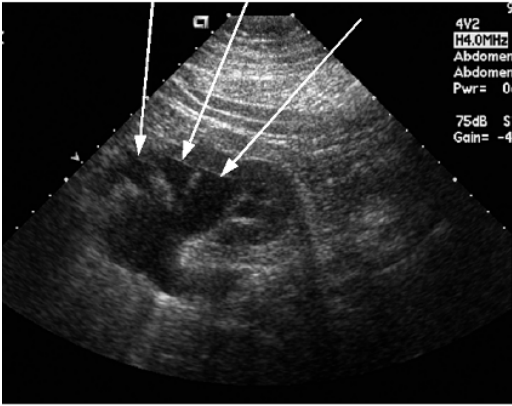

65. 附圖為右上腹之冠狀面掃描,箭號所指的構造最可能為:

(A)腎髓質(medulla) (B)腎盞(calyx) (C)腎細胞癌(renal cell carcinoma) (D)肥厚之腎柱(hypertrophic column of Bertin)